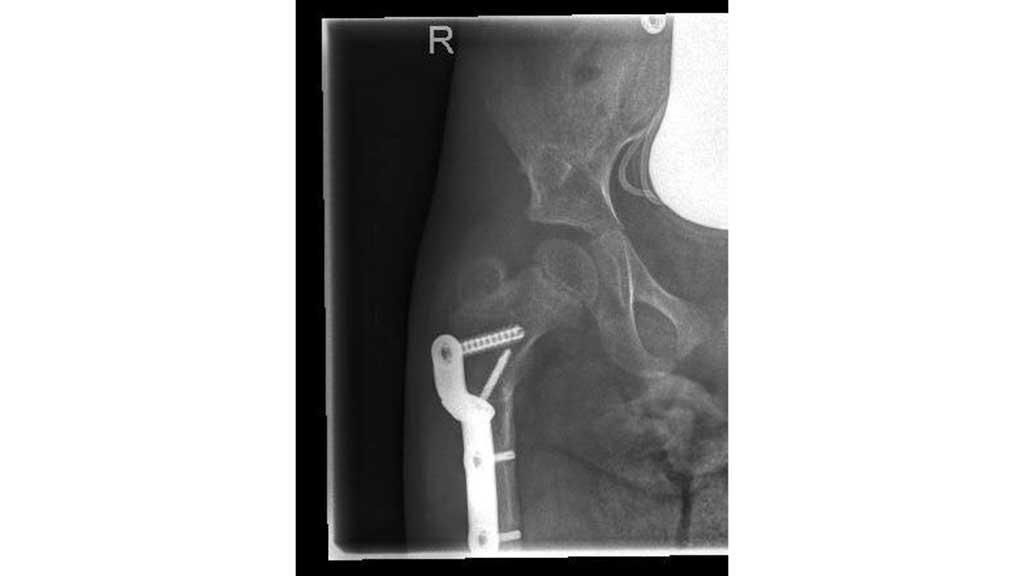

Im Frühjahr 2012 erfolgte dann die umfangreiche Hüftoperation: Adduktorentenotomie beidseits, Psoas-Tenotomie rechts, offene Reposition und DVO und Pfannendachplastik nach Dega mit Surfixplatte rechts (Abb. 8).